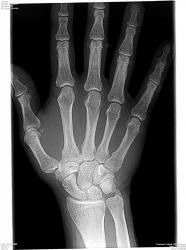

Для диагностики пневмонии, синуситов, травм и переломов, заболеваний суставов и позвоночника необходим рентген. Мы используем современный цифровой рентген, снимки выдаются сразу на месте и распечатываются на специальной фотобумаге. Вас осмотрит врач, установит диагноз, заберет анализы и назначит лечение перелома, выполнит необходимые инъекции, сделает гипс. Мифы и правда о рентгене на дому!